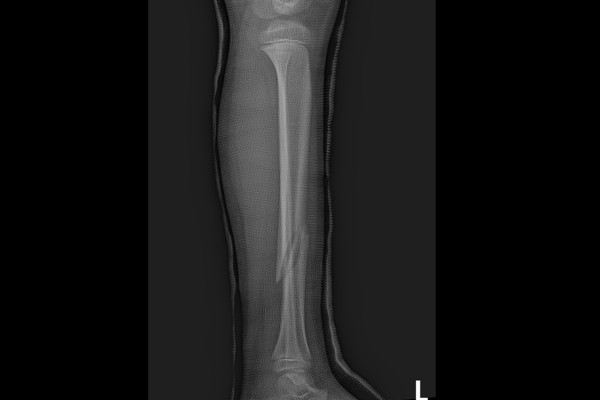

삽입물 제거 후 X-RAY 사진을 보면 정강이 뼈가 잘 회복되었음이 확인됩니다.

수술 전/후를 X-RAY 사진을 비교했을 때, 잘 회복된 것이 한 눈에 확인됩니다.

소아 골절의 경우, 성인보다 회복속도가 빠르지만, 성장판이 열려있는 상태이기 때문에 성장판이 손상되지 않도록 주의해야 합니다. 따라서 뼈에 금이가거나, 부러진 경우에는 골절 수술 경험이 많은 정형외과 전문의를 찾아 정확한 진료 및 치료를 통해 후유증 없는 올바른 치료를 받으시길 바랍니다.